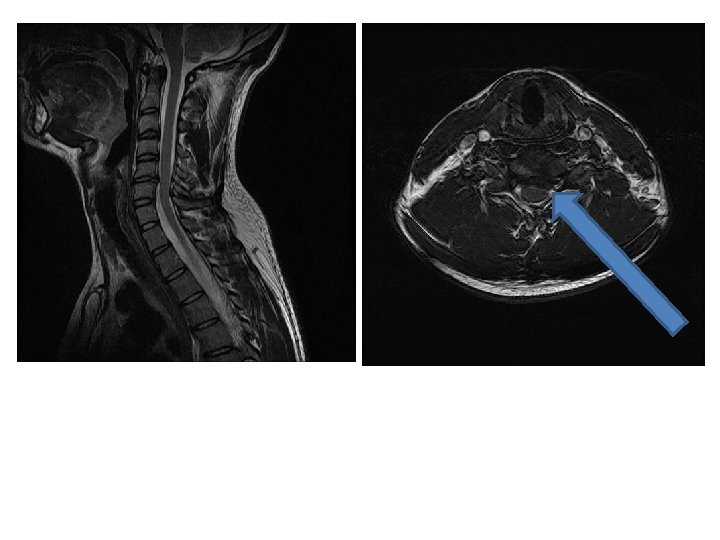

IRM en T 2 coupes sagittales

Cas clinique 2 • Examens complémentaires – EMG confirme l’atteinte neurogène C 6 droite – IRM: discopathie et hernie discale médiane et paramédiane C 5 -C 6 sans modification de courbure cervicale • Propositions de prise en charge?

Cas clinique 2 • Propositions de prise en charge – HD médiane, paramédiane – arthroplastie C 5 -C 6 – indications: sujet jeune, pas de déformation vertébrale